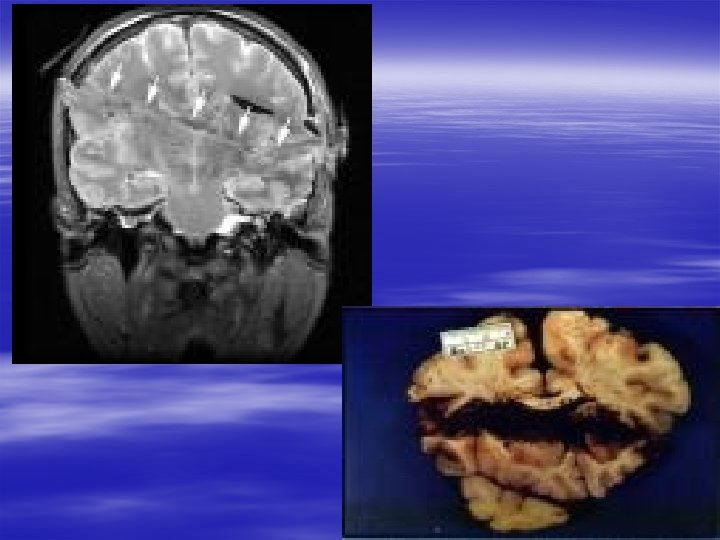

Specific Head Injuries § Diffuse Axonal Injury – Disruption of axons in white matter and brainstem – Injury occurs immediately and is irreversible – Seen after MVC or shaken baby syndrome – Usually have persistent vegetative state – CT usually normal – MRI with multiple, diffuse abnormalities